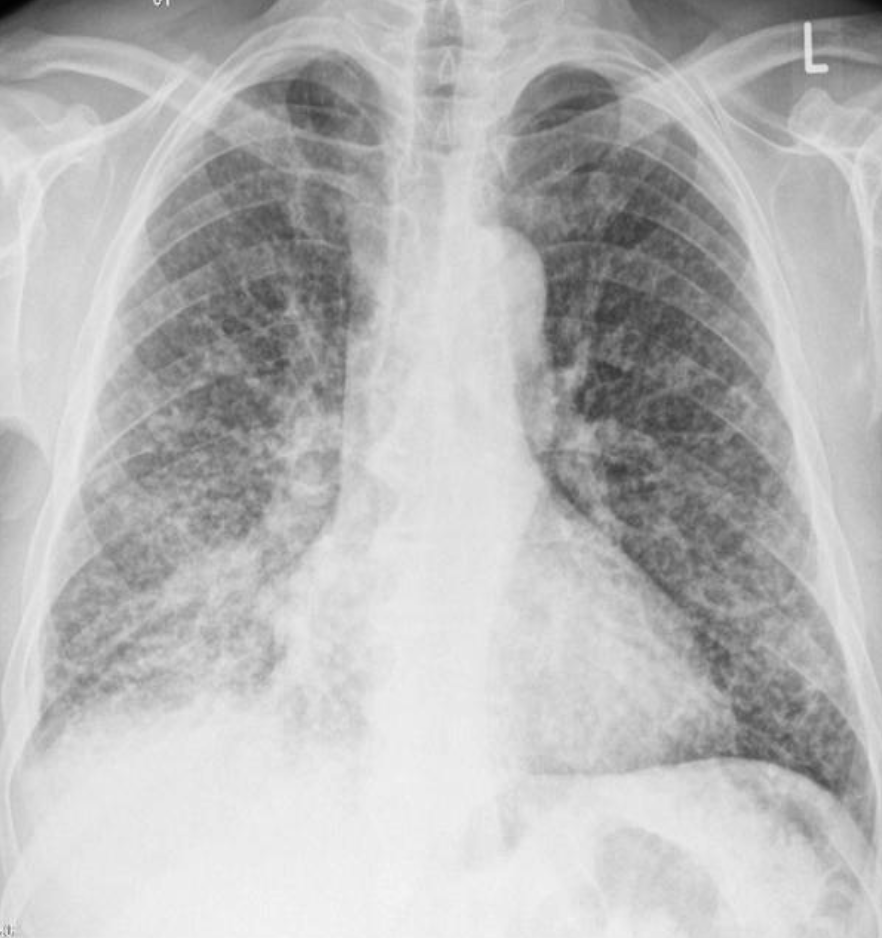

Case 13 Z

32 year female presented with fever & weight loss

Describe radiological findings

What’s the abnormal here? You should read the whole chest film PA VIEW:

- The trachea looks central.

- Heart looks normal in shape and size.

- What’s abnormal? You have all this reticular shadows and nodules all over the lungs,

Bronchitis does not give a picture like this while miliary TB is a possibility.

differential diagnosis of miliary shadow of the lung?

1- Miliary TB

2- Sarcoid

3- Diffuse metastatic lesions.

4- Lymphomas

5- Silicosis